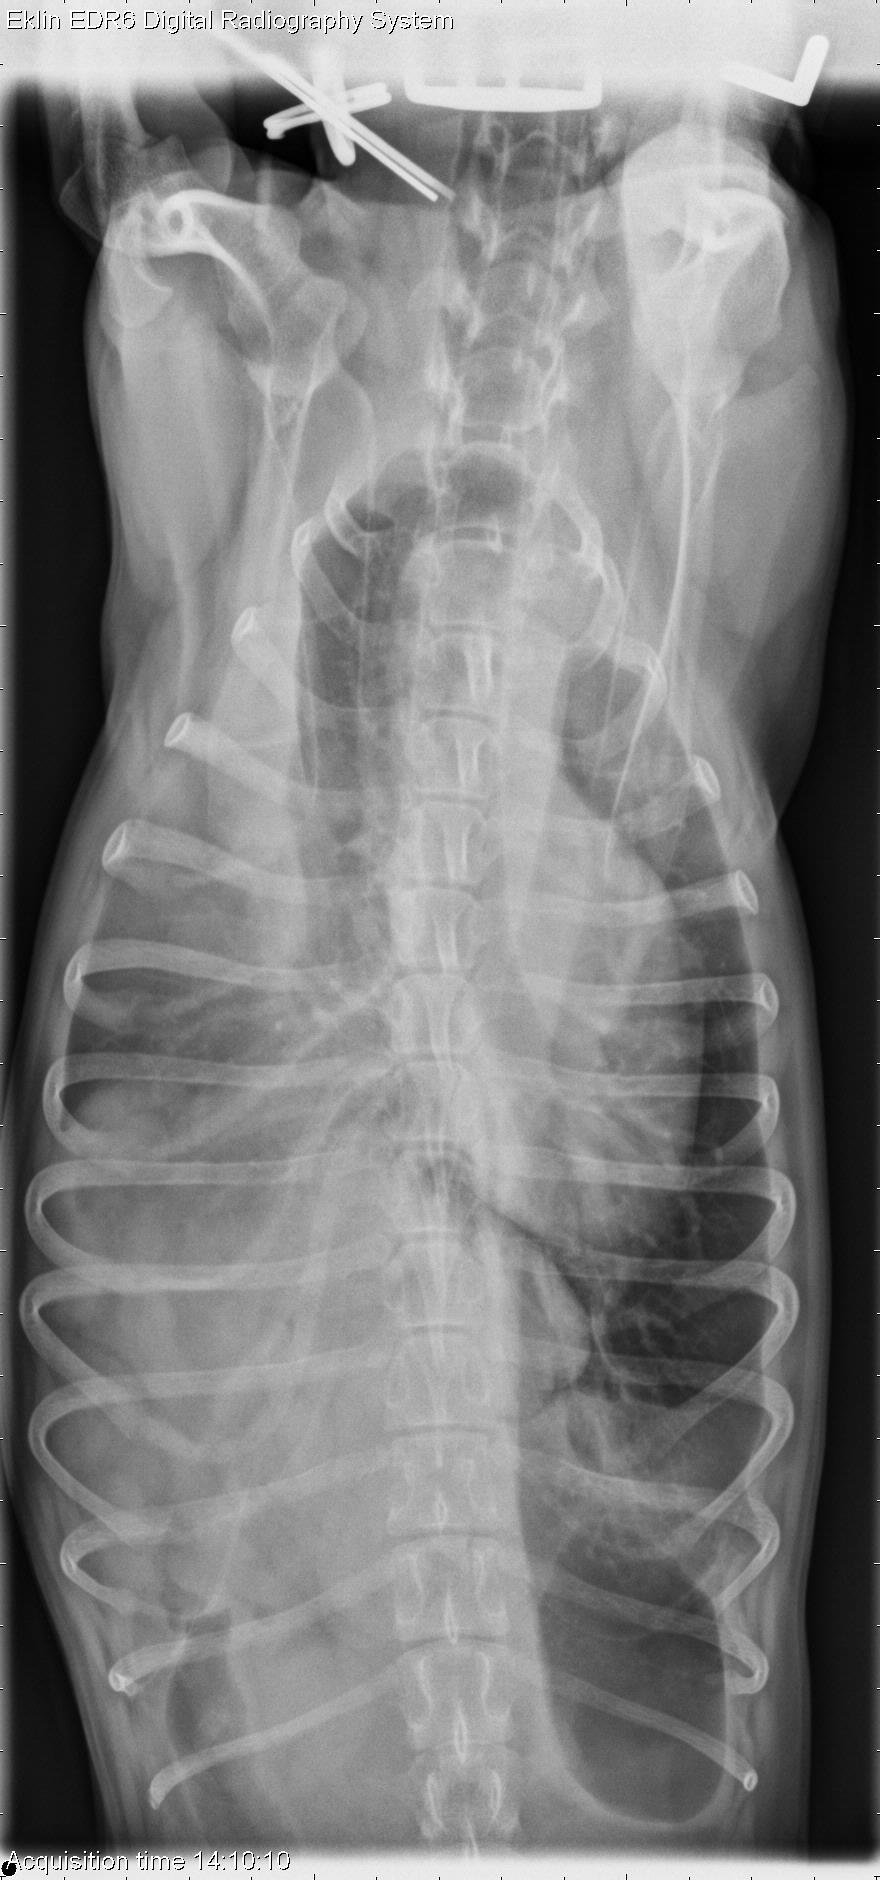

18 month old Rat Terrier

Today’s case is an 18-month-old Rat Terrier who was kicked by a horse several months ago. Presents for respiratory distress. Challenge yourself to rank your differential diagnoses.

There is increased opacity in the thoracic cavity on all projections. The lung lobe margins are rounded and retracted with visible fissure lines, indicating pleural effusion. The opacities in the thoracic cavity include soft tissue and gas opacity with a granular appearance. This is mostly present on the right side, and the diaphragm is not visible on the right. The cardiac silhouette is displaced to the left by this mass effect. The left hemithorax is more normal in appearance. There is a small volume pneumothorax visible in the left caudal thorax on the ventrodorsal projection. The normal hepatic silhouette is not visible in the abdominal cavity, and the stomach is positioned more cranially. There is poor detail in the abdomen suggesting peritoneal effusion.

Chronic diaphragmatic hernia on the right side with secondary bicavitary effusion and small volume pneumothorax. The liver and a portion of the intestine are most likely located in the pleural space.

At surgery, there were two rents in the right diaphragm with herniation of small intestine and liver.